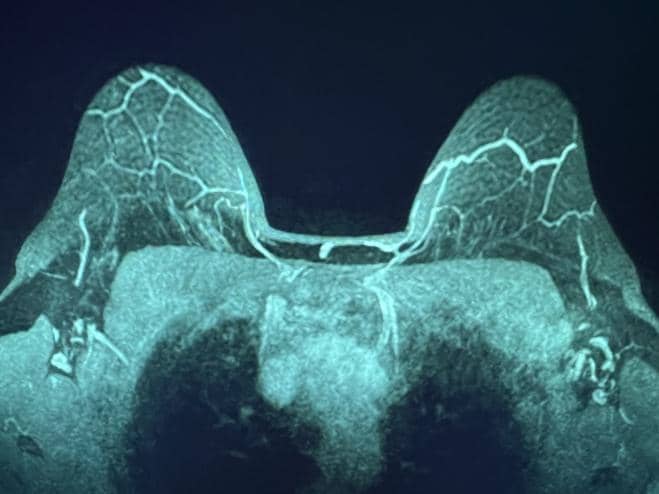

Şekil 1. MRG MIP, NAC'ye seyahat eden, meme başından üstün (solda) ve meme başı seviyesinde (sağda) IMP'leri gösterir.

Birden fazla dilimin ortalamasını alan yaygın bir yeniden format olan meme MRG MIP (maksimal yoğunluk projeksiyonu) görüntüleri, NAC'ye baskın kan akışını açıkça görselleştirdi (Şekil 1). Bilateral dominant IMP'ler, 2. ve/veya 3. interkostal boşluklarda (ICS) sternal sınır boyunca pektoralis majör kasından yayılır. Daha sonra, damarlar memenin deri altı dokusunda öne doğru seyretti ve NAC'nin yakınında sonlandı.

Önemli NAC kan kaynağını korumak için IMP-NSM cerrahi tekniği, önemli adımları içeren daha önce yayınlanmıştır. 1, 11, 12 Kontrastlı meme MRG, preoperatif evreleme için elde edilirse, en iyi MIP görüntülerinde görselleştirilen NAC kan akışını açıkça gösterebilir. Bu, tipik olarak IMP'den iki taraflı olarak, genellikle sternal sınır boyunca 2. veya 3. ICS'den kaynaklanan baskın NAC kan kaynağını gösterir (Şekil 1).

2.-4. ICS, sternal sınırın 1 cm lateralinde cilt üzerinde işaretlenir, bu da ana IMP damarlarının tanımlandığı ve pektoralis majör kasının önünde korunduğu ortak alanları gösterir. IMP-NSM tekniği, meme MRG'si olmadan, bu olağan yerleri işaretleyerek ve daha sonra bu alanlarda dikkatli bir diseksiyon yaparak gerçekleştirilebilir; bununla birlikte, varsa, meme MRG görüntüleri IMP kan temini hakkında yararlı bilgiler sağlayabilir ve ameliyattaki yeri tahmin edebilir. IMP-NSM, NAC'ye baskın IMP kan akışını korumak olarak tanımlanır; bununla birlikte, teknik, ilişkili ACN duyusal dallarına ek olarak, sternal sınır boyunca görselleştirilen ve vasküler beslemeye katkıda bulunabilecek ek küçük baskın olmayan IMP damarlarının korunmasını içerecek şekilde gelişmiştir. (Şekil 1 ve 2).